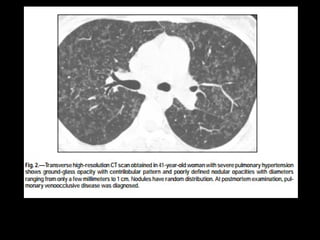

Tomografia computadorizada

Achados parenquimatosos: dependem da etiologia

e mecanismo da hipertensão:

Perfusão em mosaico, vidro fosco, espessamento

septal e nódulos centrolobulares.

Derrame ou espessamento pleural, e, em pacientes

com HAP grave, pequeno derrame pericárdico.

HAP pós-capilar

Doença pulmonar venoclusiva

Definição: trombose venosa pulmonar com sinais e

sintomas de HAP;

Associação com medicamentos(bleomicina e

mitomicina), HIV, TMO e sarcoidose;

Na adolescência a incidência é igual entre os sexos,

mas na fase adulta/velhice há discreto predomínio

de homens;

Patologia: estenose ou obliteração parcial das veias

e vênulas pulmonares por tecido fibroso

proveniente da íntima.